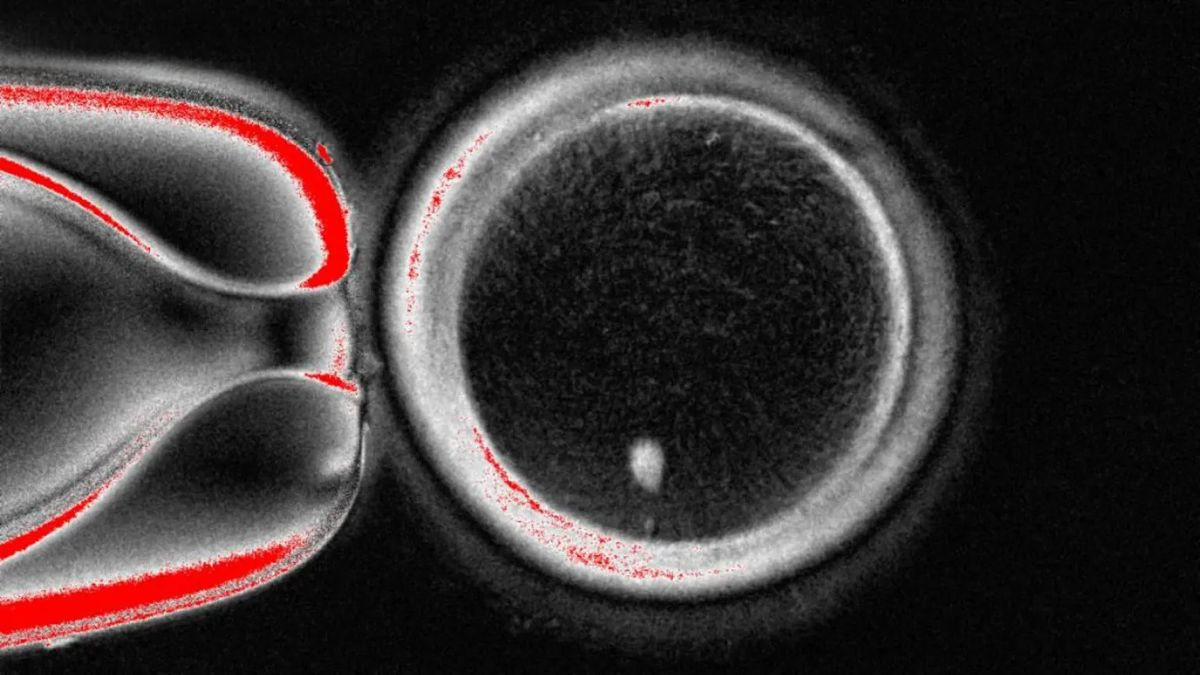

Σε ένα επιστημονικό επίτευγμα που προκαλεί ενθουσιασμό αλλά και έντονες συζητήσεις, ερευνητές από το Oregon Health and Science University κατάφεραν να...